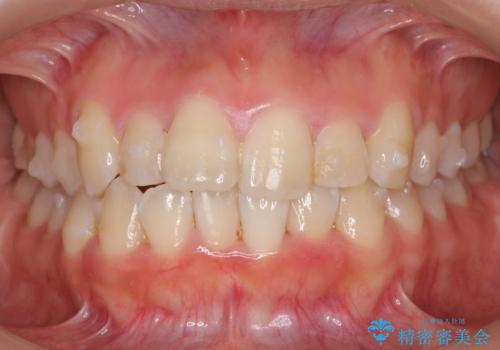

上下の前歯のがたつき 歯を抜かずに矯正

- 上下の前歯のがたつきを主訴に来院。

歯を抜かずに前歯を揃えています。

奥歯を後ろに下げたりなどはしていません。

奥歯を外に広げ、前歯中心に歯を少し削っていますが、健康には問題ない範囲で行なっています。